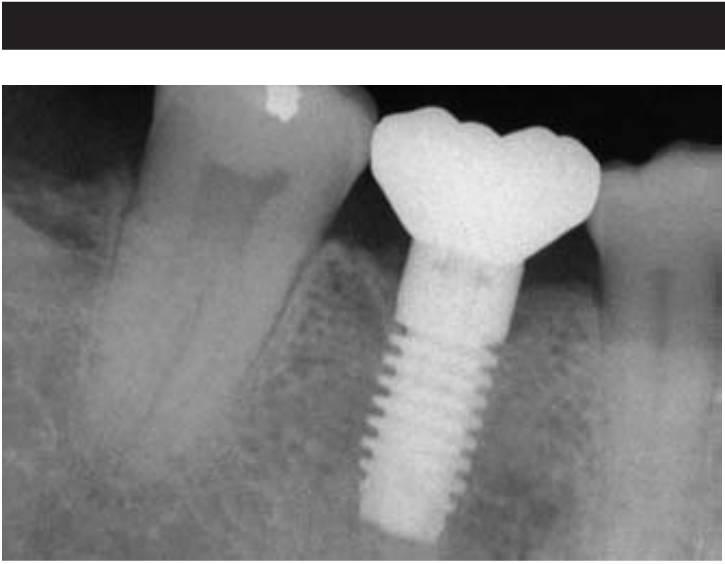

Un tratamiento opcional para sustituir a un solo diente perdido es un implante dental unitario (fig. 1-8). Durante años, los pacientes debían aparcar sus deseos y aceptar las limitaciones de una PPF. Sin embargo, muchos sienten que el método más natural de reemplazar un diente es emplean do un implante, más que preparando los dientes adyacentes y uniéndolos con una prótesis. Los motivos principales para sugerir el uso de las PPF fueron su facilidad clínica y su reducido tiempo de tratamiento. En cualquier caso, si se expandiera este concepto, las extracciones reemplazarían a las endodoncias y las dentaduras podrían incluso reemplazar a las ortodoncias. El motivo principal para sugerir o llevar a cabo un tratamiento no debería tener relación con el tiempo de tratamiento o la dificultad del procedimiento, sino que debería ser la mejor solución posible a largo plazo para cada individuo.

Desde 1993 hasta la fecha, los estudios sobre la supervivencia de los implantes individuales han validado este procedimiento como el método de sustitución dental más predecible. En la literatura existen más publicaciones sobre el implante dental unitario que sobre cualquier otro método de sustitución dental35'47, y todos los estudios mostraron una media de supervivencia más alta en los implantes den tales individuales. Goodacre y cols, publicaron una revista literaria médica desde 1980 hasta 2001 y observaron que la media de éxito del implante dental unitario era hasta del 97% , más alta que cualquier otra restauración implantológica. En 1995, Haas y cols, estudiaron 76 implantes den tales unitarios sobre un período de 6 años y observaron una media de supervivencia del 97% y un 2 % de pérdida del implante. Fugazzotto evaluó 1.472 implantes en un período de 13 años y observó una media de supervivencia del 97 % durante ese período.

Aunque la sustitución dental posterior individual es un tratamiento alternativo relativamente reciente, se han publicado numerosos estudios desde 1990, y las medias de supervivencia referidas van desde el 9 4 ,6 % hasta el 100% sobre períodos que van desde 1 año hasta 15 años. En estos estudios la media de pérdida del implante es del 2,8% sobre un período de 5 años. En comparación, la media de fracaso en las PPF es del 2 0 % sobre 3 años, y se pueden esperar fracasos del 50 % sobre períodos de 10 años. como resultado, el implante dental unitario exhibe la mayor media de supervivencia entre las sustituciones dentales individuales. Y tan importante es que ningún estudio refiere la pérdida de un diente adyacente, lo que es una ventaja considerable. Por otra parte, no se ha determinado de manera adecuada la longevidad de la pieza o corona implantaría al no extenderse tanto estos estudios como los de otras opciones de tratamiento.

Salvo algunas limitaciones y desafíos clínicos evidentes, el implante dental unitario representa un tratamiento de elección desde el doble punto de vista de la salud y el valor. Cuando los dientes adyacentes están sanos, o el paciente rechaza su preparación para la fabricación de una unidad tradicional de restauración de tres unidades, un implante dental posterior unitario es una solución excelente (fig. 1-9). Las ventajas relacionadas con la salud de esta modalidad respecto a la restauración fija parcial se enumeran en el cuadro 1-2 e incluyen disminución del riesgo de caries y de enfermedad periodontal, disminución del riesgo de pérdida de un pilar dental por caries o fracaso del tratamiento endodóncico y mejoría estética (fig. 1-10).